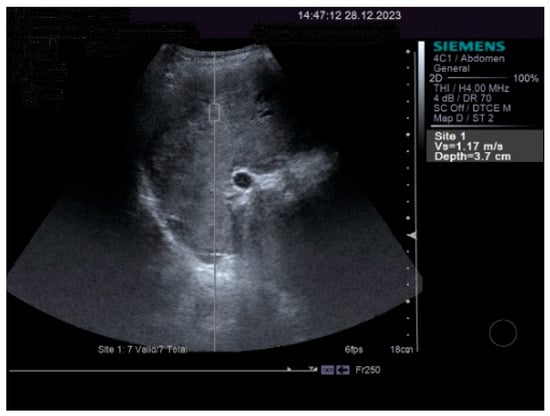

On physical examination, a mild tenderness of the right upper abdominal quadrant, a firm hepatomegaly, a palpable inferior pole of the spleen and a slight increase in abdomen volume were found. No other liver stigmata were noticed. The abdominal duplex ultrasound examination, performed with Siemens high-resolution equipment, showed hepatomegaly with a discrete irregularity of the liver surface, heterogeneity of the liver texture, the caudate lobe at the upper limit, filiform hepatic veins, massive thickening of the gallbladder wall, ascites in small quantity and mild splenomegaly with turbulence of the venous flow in the hilum. The question about liver cirrhosis was asked. Various aspects of the 2D ultrasound examination of the liver are depicted in Figure 2.

The pulsed Doppler ultrasound revealed a patency of the main portal vein as well as of the left and right portal branches and decreased, demodulated hepatopetal portal venous flow, with mildly decreased respiratory variability in the amplitude of the portal vein flow. The Dopler aspects of the liver and spleen are illustrated in Figure 4.

The measurements of the resistivity index of the hepatic artery at the liver hilum revealed increased values (HARI = 0.79). However, the liver elastography demonstrated a low stiffness. The measurements were made using the acoustic radiation force impulse (ARF)I method, by point shear wave (p SWE) elastography, and the obtained median value was 1.24 m/s, IQR = 0.12, equivalent to an F2 Metavir fibrosis score. Therefore, the diagnosis of liver cirrhosis was highly improbable. The elastography of the right liver lobe performed by the ARFI method, pSWE, is presented in Figure 5.

Abdominal MRI study confirmed the hepato-splenomegaly, ascites and the patency of the portal vein system. In addition, small veno-portal shunts were highlighted at the periphery of both hepatic lobes. Various MRI features are depicted in Figure 6, Figure 7, Figure 8 and Figure 9.

Figure 2. The 2D ultrasound aspect of the liver: perihepatic ascites (right,left), caudate lobe at the upper limit (middle).

Figure 6. MRI featuring perihepatic and perisplenic ascites.